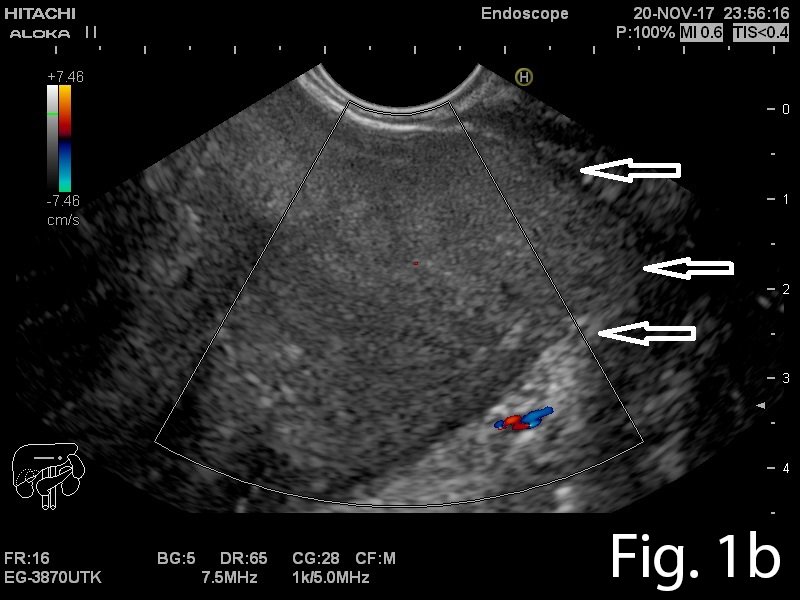

A 46-year old man presented to the gastrointestinal clinic complaining of dysphagia, regurgitation and a sensation of a lump in the throat, symptoms which had progressively worsened over the previous year. Upper GI endoscopy revealed a giant soft mass within the esophageal lumen, with a smooth surface covering, originating from the cervical esophagus, with a positive ”squeeze sign” (Video 1). EUS was performed and showed a giant mobile lesion occupying the esophageal lumen, with hyperechogenic structure, suggestive of a lipoma (Figure 1ab). Contrast-enhanced EUS did not depict any signals inside the subepithelial mass in the early arterial or late venous phases(Figure 1c). In order to define the surgical approach, a CT of the neck, thorax and abdomen was performed and it revealed the submucosal pedunculated tumor mass, confirming the diagnosis of lipoma (Figure 2).

Figure 1a-b. EUS showing a hyperechogenic lesion with a smooth margin arising from the submucosal layer of the esophagus. 1c. Contrast-enhanced EUS indicated completely absent signals, for both the early arterial and late venous phases.